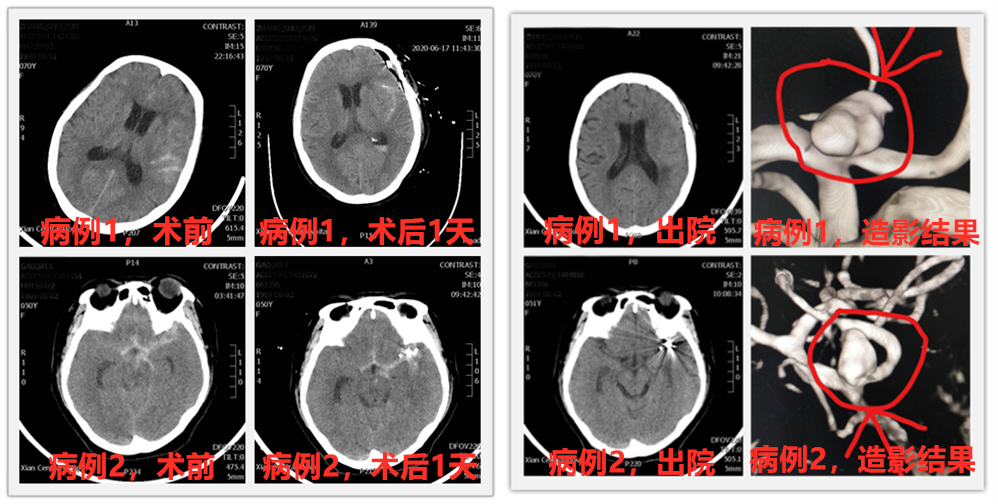

说完这么多理论,这不,91论坛 神经外科最近就有两位蛛网膜下腔急性出血患者,经过脑血管造影诊断,查出分别是颅内不同血管上的动脉瘤,根据病情需要及患者家属要求,科室施展十八般武艺对付这个“坏家伙”,分别为两位患者安排了开颅动脉瘤夹闭术及颅内动脉瘤介入栓塞术,经过积极治疗,患者都康复出院,回归正常生活,获得了患者及家属的一致好评。